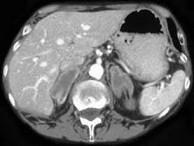

问题 男,65岁,体检时超声发现双侧肾上腺肿块,CT检查如图所示,请结合图像,选择最佳答案()

选项 A.双侧肾上腺转移瘤 B.双侧肾上腺结核 C.双侧嗜铬细胞瘤 D.双侧肾上腺增生 E.双侧肾上腺腺瘤

答案 A